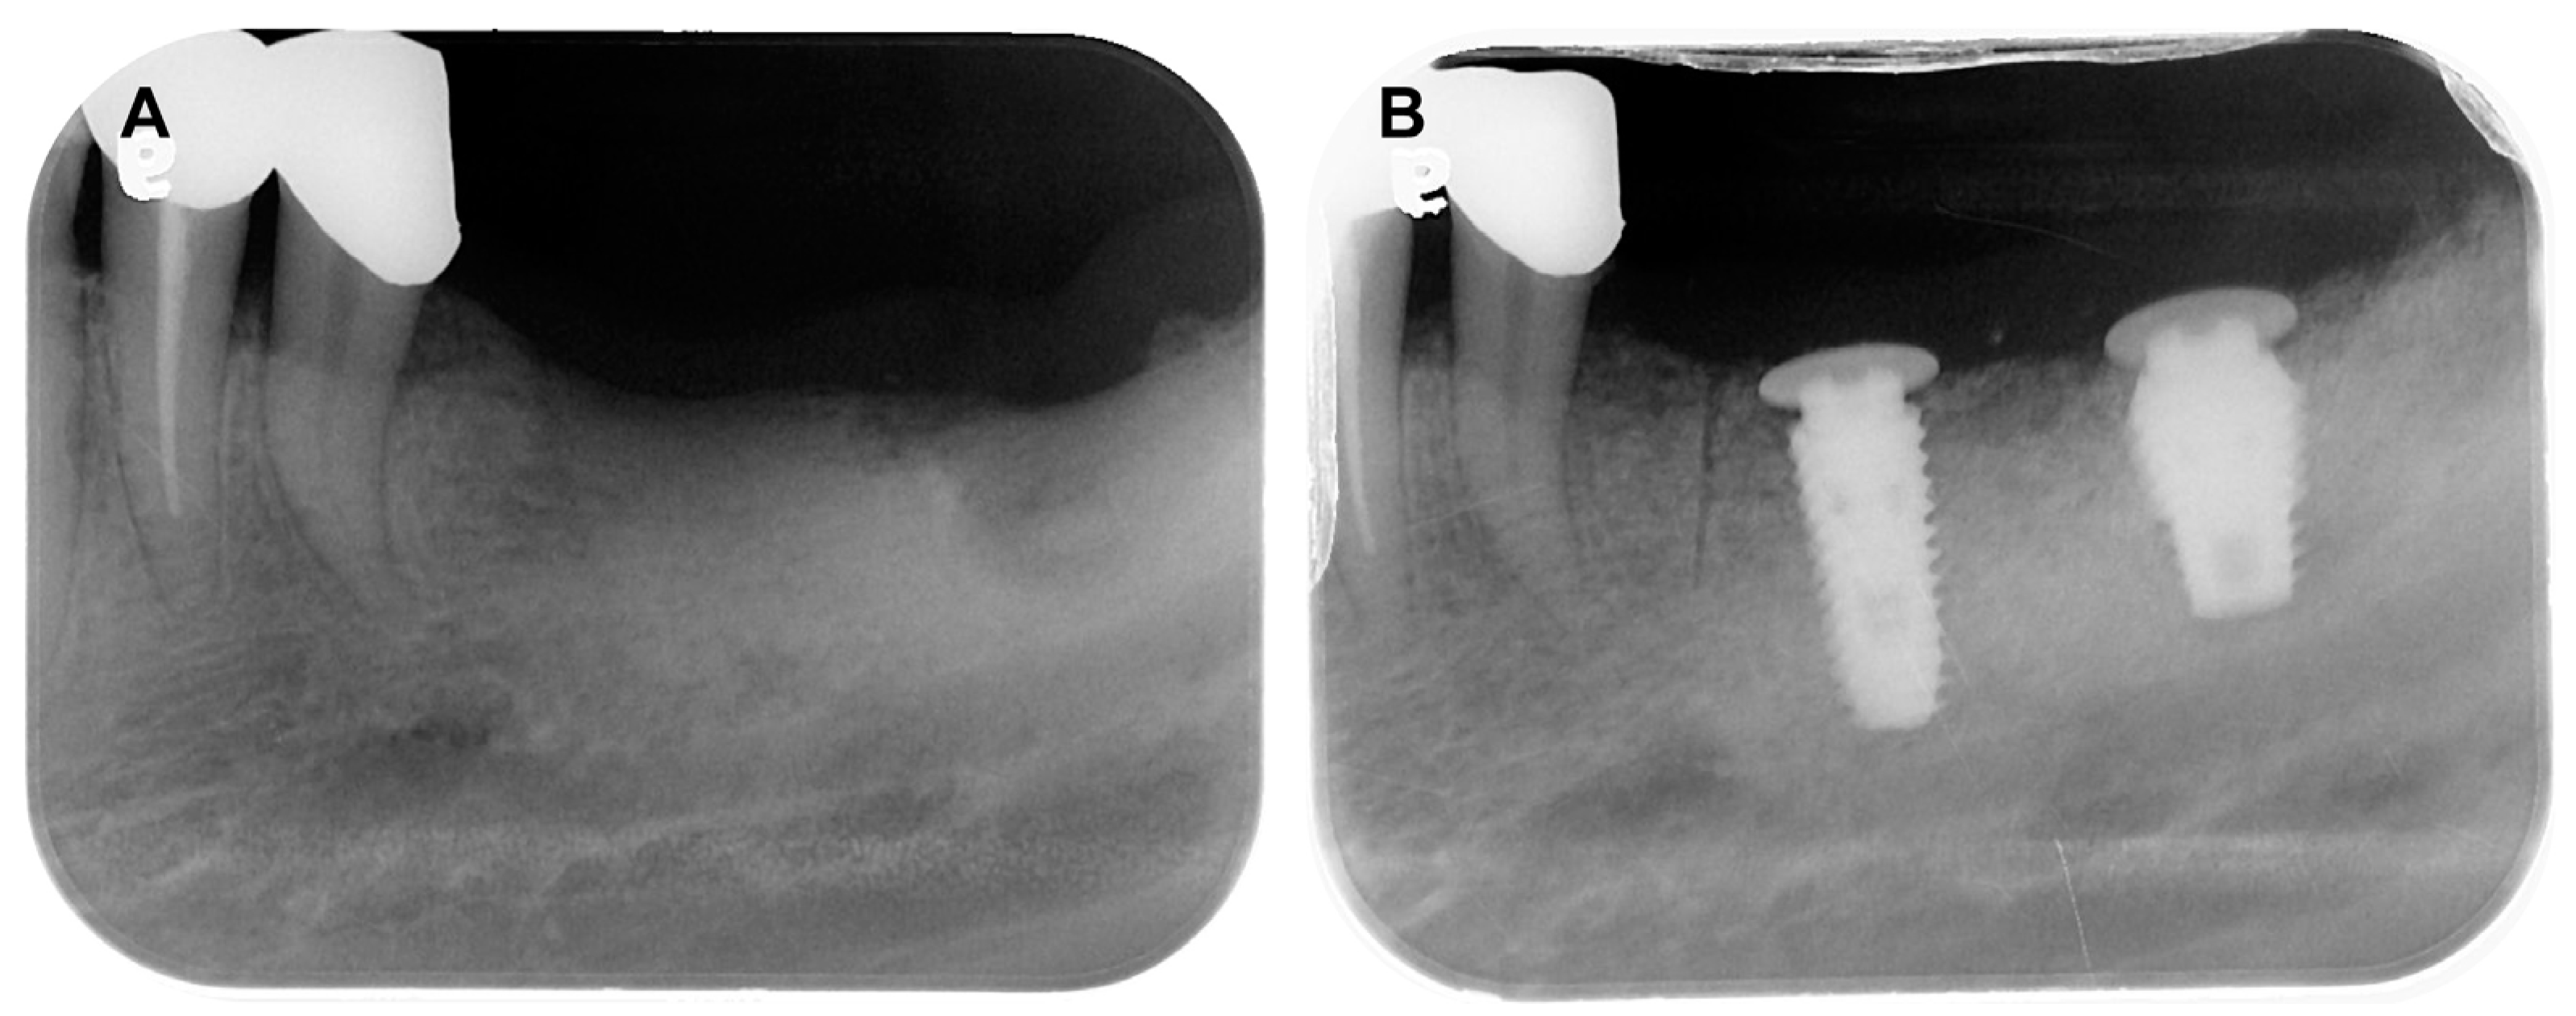

A 69-year-old female patient visited the dental clinic of Daegu Catholic University Medical Center to restore a missing mandibular left first molar and second molar (Figure 8A). The patient had a medical history of mild diabetes and hypertension, but she was not taking any medications which needed to be discontinued during the implant procedure. The patient was a non-smoker. Through consultation with the patient, it was decided that two implants would be placed. As a surgical method, flap operation was planned for vertical and horizontal bone grafting and implant placement. After the intraoral and radiological examination of the patient, scaling was performed before implant placement. The patient received the same pharmacologic protocol of the patient of case 1. A 4.5 × 10.0 mm and a 5.0 × 8.5 mm implant (AR fixture; Biotem, Seongnam, Republic of Korea) were placed, respectively (Figure 8B). Each implant was placed with the proper initial fixation torque of 30 N/cm2. After a sufficient healing period of 3 months, it was decided the prosthetic treatment procedure would commence.

Figure 8. (A) Pre-operative intraoral periapical radiograph, (B) Post-operative intraoral periapical radiograph.